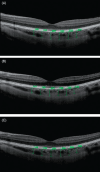

Figure 3

Choroidal thickness measurements obtained before (A), 1 hour after (B), and 3 hours after (C) oral caffeine consumption (200 mg capsule) (from Zengin et al.; reprinted with permission from Taylor & Francis Informa UK Ltd-Journals)